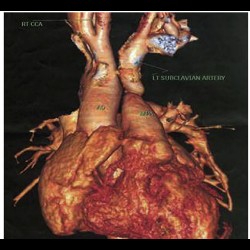

Cardio Thoracic Imaging

Isolated left brachiocephalic trunk arising from the main pulmonary artery with right aortic arch

Cardio Thoracic Imaging

Isolated left brachiocephalic trunk arising from the main pulmonary artery with right aortic arch